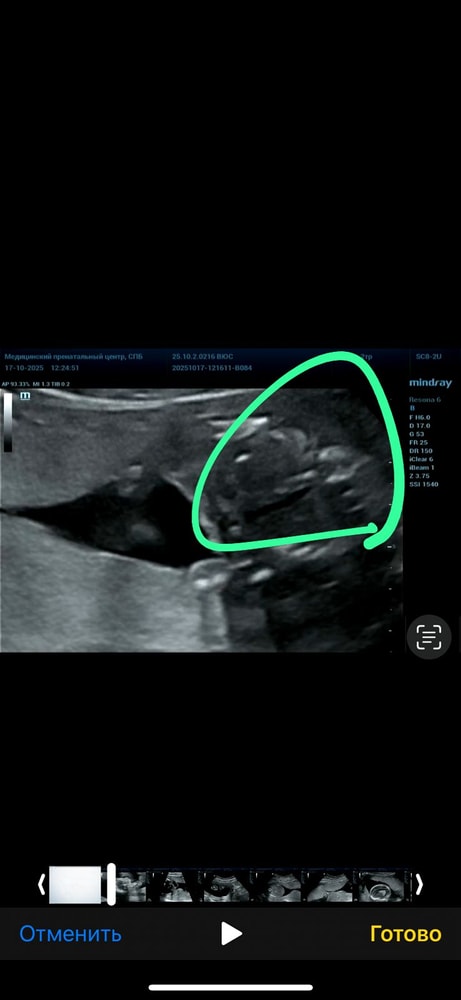

Анализы, скринингиВот и сделала я второй скрининг, получила видео с узи, когда смотрела узи (доктор не разу не выключал экран) то по видео поняла, что мальчик 🤣 нам дали конвертик с полом, на котором уже было все напечатано (не от руки) и запечатан с двух сторон, переживаю была ли ошибка в конверте. Я вижу мальчика 🤣 а на конверте девочка. У меня есть два сына и я уже боюсь узи 🤣

Просто мне кажется что там выше рядом еще третье что-то 🤣